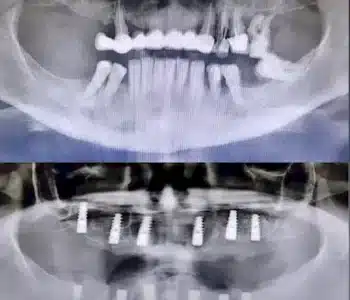

Dr. Seden Aksu is a specialist in modern implantology and surgical dentistry with extensive experience in the management of complex clinical cases. In her practice, she applies comprehensive surgical planning, minimally invasive techniques, and advanced regenerative technologies aimed at restoring both the function of the dentoalveolar system and the aesthetics of the smile. Dr. Aksu has significant experience in performing implant procedures, bone augmentation, and periodontal surgery, including the treatment of patients with severe bone loss. The primary goal of her work is to achieve stable, long-term outcomes in implant rehabilitation and the restoration of oral tissue health.